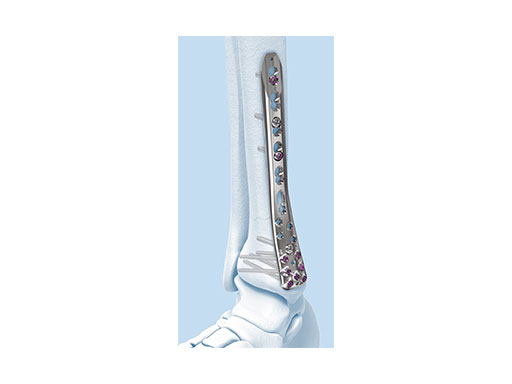

The new Variable Angle LCP Ankle Trauma 2.7/3.5 system was developed to overcome these shortcomings. The low-profile plates feature variable angle locking screw technology and offer more options for screw placement to address a wider range of fracture patterns and to accommodate varied patient anatomies. In addition, these anatomically accurate plate designs simplify minimal invasive plate insertion and indirect reduction techniques (push-pull applications). The plates are available in stainless steel and are primarily for the treatment of articular injuries. The VA-LCP Lateral Distal Fibula Plates are also provided in titanium.

The Combi holes in the Variable Angle LCP plate shaft combine a dynamic compression unit hole with a variable angle locking screw hole. Due to the smaller sized and more numerous fixation options distally with 2.7 mm VA screws, the fixed-angle construct provides advantages for small metaphyseal segments where traditional screw fixation can be limited. The screw trajectories are optimized to support the distal articular surface. The multiple variable angle locking holes in the plate head accept 2.7 mm VA locking, 2.7 mm locking, 2.7 mm cortex, and 2.7 mm metaphyseal screws. The latter has a low profile screw head to avoid soft tissue irritations and can be used to pull the plate to the bone. Due to the numerous screw possibilities, it is important that the surgeon is familiar with which screws can be used in which plate holes. The system includes guide blocks for all plates (except T and L plates) for inserting screws in the plate head at nominal screw angles (Fig 1a-c). K-wire holes in the plate head and shaft tip accept K-wires up to 1.6 mm. They can be used to temporarily reduce articular fragments, and to confirm the location of the plate relative to the distal tibia and fibula.